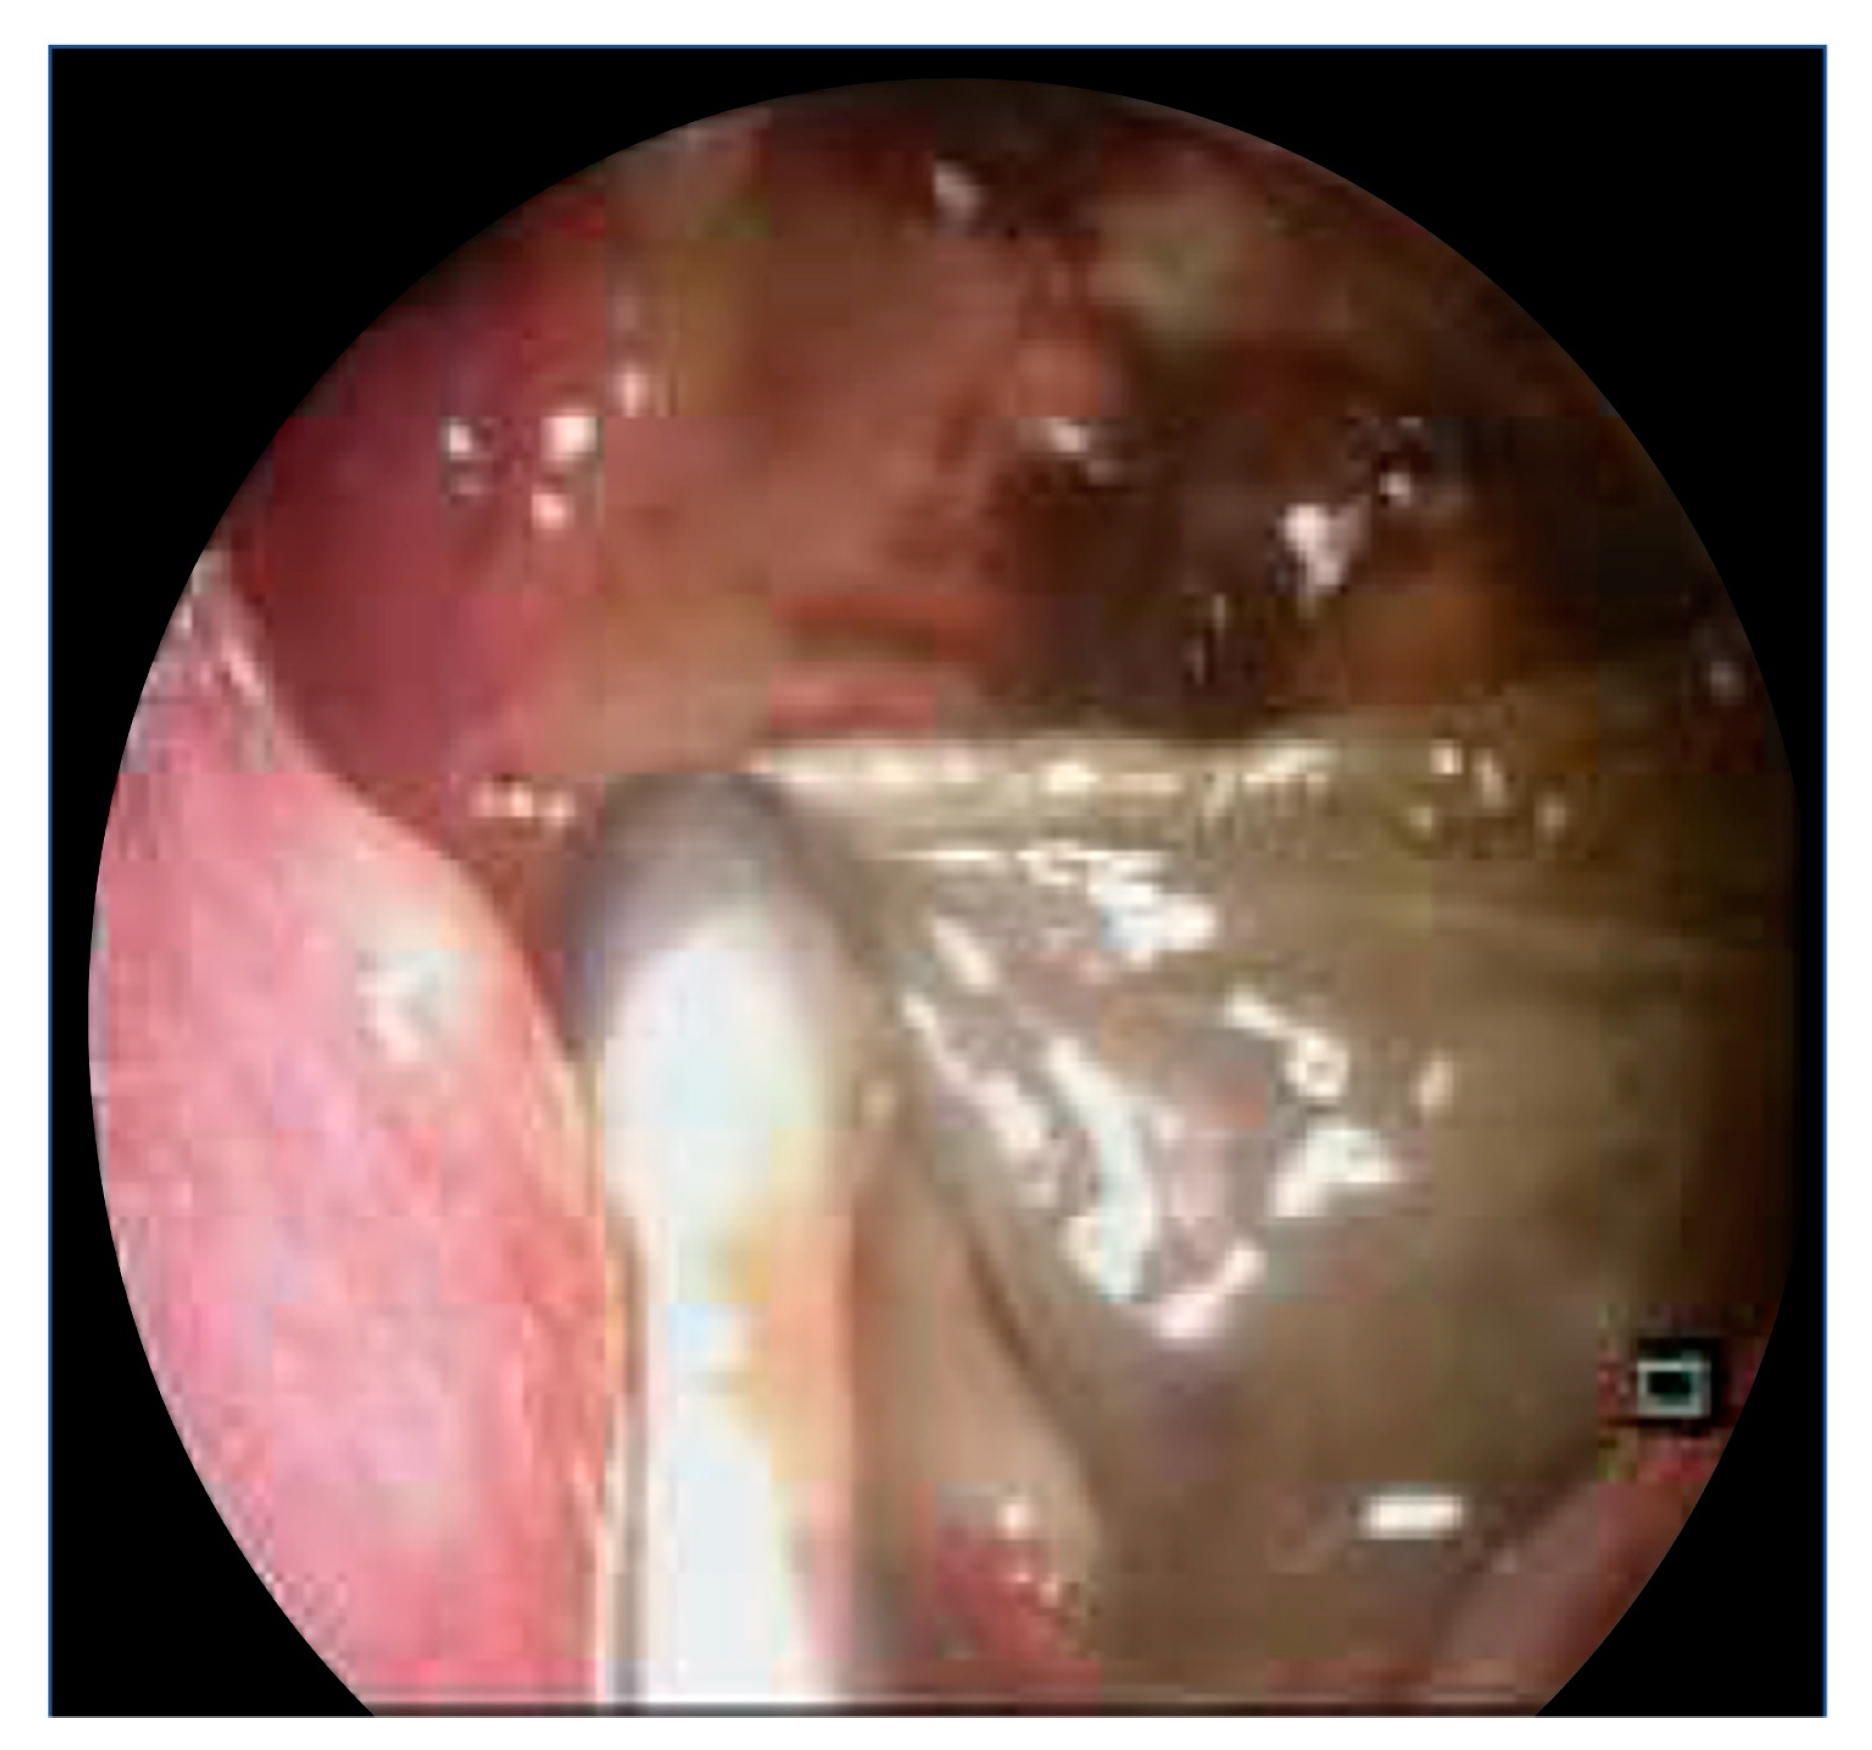

The patient underwent Left Endoscopic Sinus Surgery (Middle Meatal Antrostomy). Intra-operatively, the left maxillary sinus was filled with turbid brown fluid and dusky mucosa (Figure 4). There was no frank pus. The sinus was thoroughly irrigated with normal saline. Histology of the unhealthy mucosa revealed fibrotic subepithelial stroma and acute-on-chronic inflammatory cellular infiltrates with foci of dystrophic calcification. Tissue cultures grew Streptococcus constellatus and Citrobacter koseri. There were no fungal elements seen on fungal smear or culture.

Figure 4.

Endoscopic clinical image depicting intraoperative findings of denuded left maxillary sinus mucosa, with some remnant dusky mucosa.